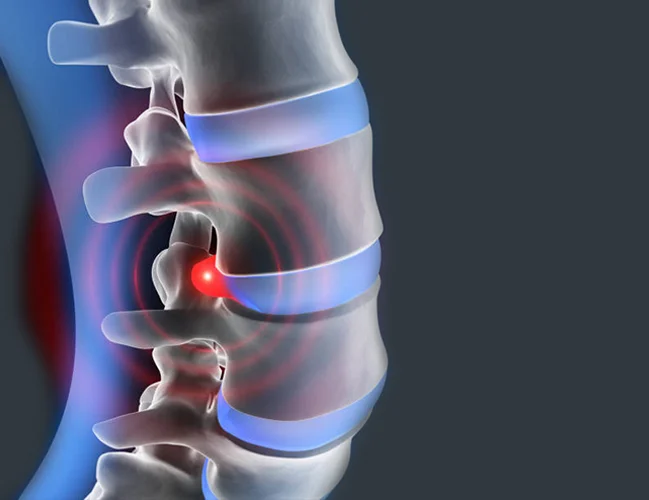

A herniated disc, also referred to as a slipped disc, ruptured disc, or disc herniation, is one of the most common causes of back pain. Often, people visit a spine specialist for back pain and unknowingly have a herniated disc. Herniated discs affect the vertebrae, the bones that make up your spine, and the spinal discs, which provide support and flexibility to your back.

A bulging disc in the lower back protrudes into the spinal canal, leading to lower back pain, leg pain, tingling, or numbness.

Lumbar disc herniation happens when discs between vertebrae shift or rupture, compressing spinal nerves. Symptoms include lower back pain, leg weakness, and numbness.

Lumbar stenosis is the narrowing of the spinal canal in the lower back, compressing nerves and causing leg pain, numbness, or weakness.